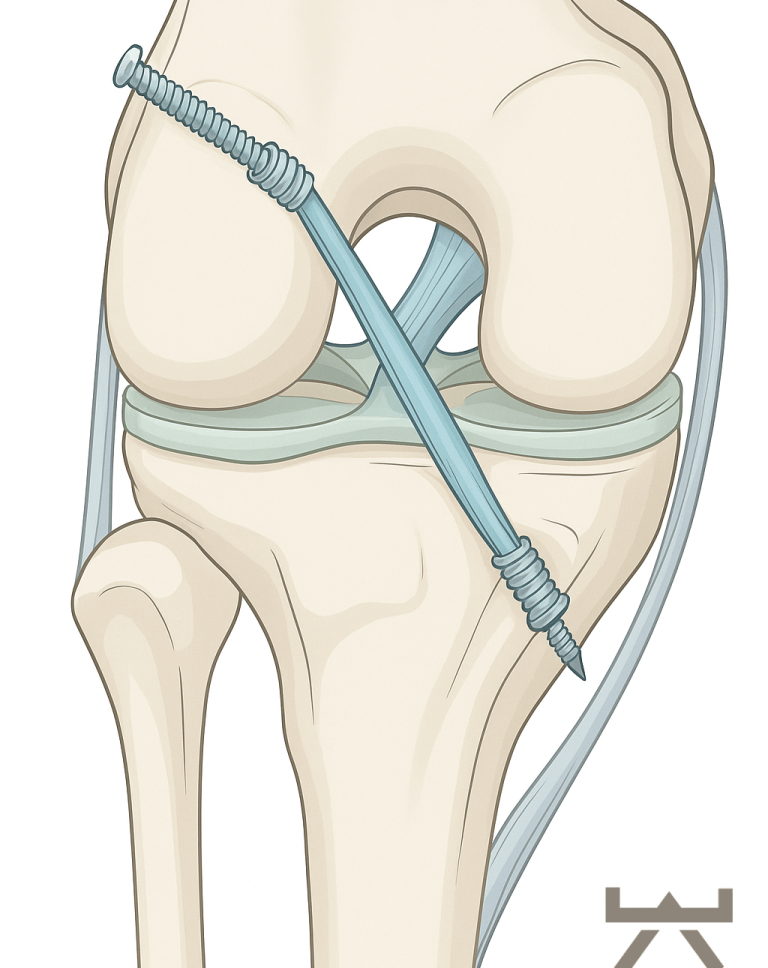

Während der Kreuzbandplastik wird das vorderste Kreuzband durch körpereigenes Sehnengewebe ersetzt. In den meisten Fällen findet die Operation arthroskopisch (mittels einer Gelenkspiegelung) statt. Als Transplantat für das Kreuzband werden vom Patienten entweder Teile der Beugesehnen (Semitendinosus-/Gracilis Sehne), oder das mittlere Drittel der Kniescheibensehne (Patellarsehne unterhalb der Kniescheibe oder Quadriceps Sehne oberhalb der Kniescheibe) entnommen. In seltenen Fällen ist ein Allograft (Spendersehne) oder ein Ersatz aus Synthetik Material notwendig. Es werden Bohrkanäle durch den Unterschenkel- und den Oberschenkelknochen vorgenommen, durch die das Transplantat dann durchgezogen und anschließend befestigt wird.

Bohrkanäle

Transplantatdurchzug